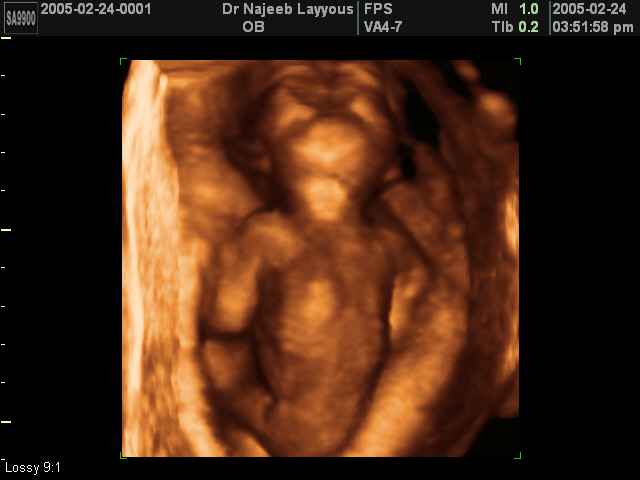

- لقطات فيديو للجنين بجهاز الموجات فوق صوتية رباعي الأبعاد

- صور لوجه الجنين في داخل الرحم

- صور لتصرفات الجنين داخل الرحم

صور لأعضاء الجنين بجهاز الموجات فوق صوتية ثلاثي الأبعاد | الدكتور نجيب ليوس